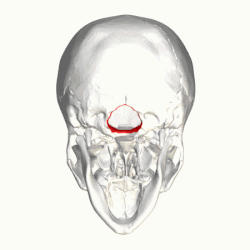

Chiari malformation

In neurology, the Chiari malformation (/kiˈɑːri/ kee-AR-ee; CM) is a structural defect in the cerebellum, characterized by a downward displacement of one or both cerebellar tonsils through the foramen magnum (the opening at the base of the skull).

By convention, the cerebellar tonsil position is measured relative to the basion-opisthion line, using sagittal T1 MRI images or sagittal CT images.[31] The selected cutoff distance for abnormal tonsil position is somewhat arbitrary, as not every person will be symptomatic at a certain amount of tonsil displacement, and the probability of symptoms and syrinx increases with greater displacement; however, greater than 5 mm is the most frequently cited cutoff number, though some consider 3–5 mm to be "borderline"; pathological signs and syrinx may occur beyond that distance.[31][32][33] One study showed little difference in cerebellar tonsil position between standard recumbent MRI and upright MRI for patients without a history of whiplash injury.[25] Neuroradiological investigation is used to rule out any intracranial condition that could be responsible for tonsillar herniation first. Neuroradiological diagnostics evaluate the severity of crowding of the neural structures within the posterior cranial fossa and their pressure against the foramen magnum. Chiari 1.5 is a term used when both brainstem and tonsillar herniation through the foramen magnum are present.[34]